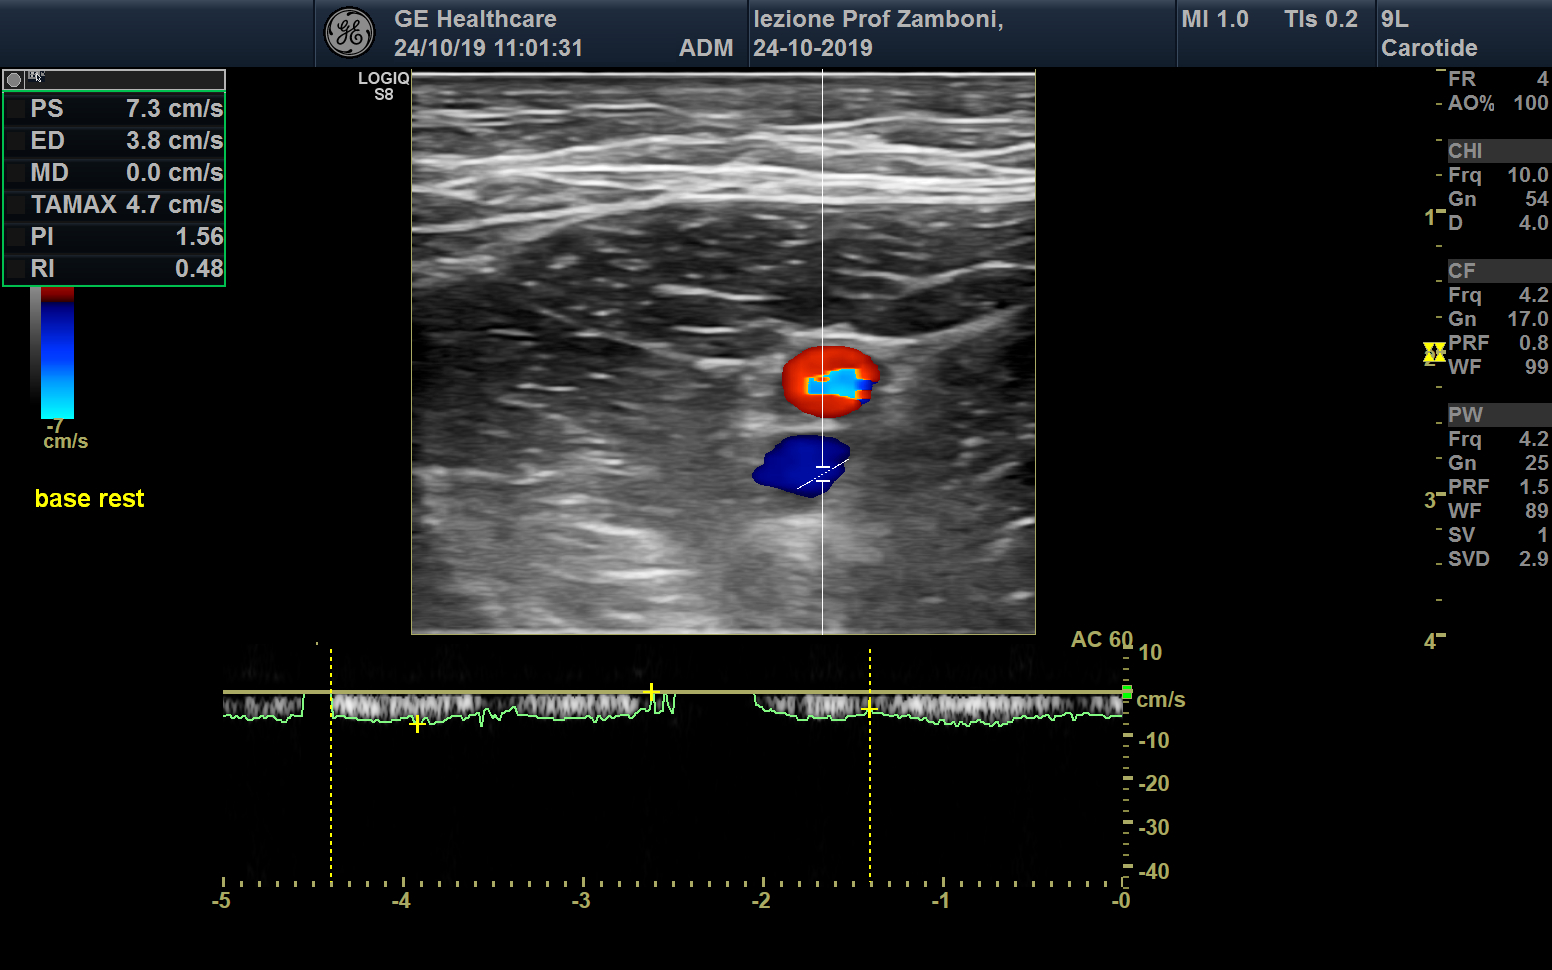

PW V. Femorale base

JPEG image icon PW V. Femorale base.jpg — JPEG image, 576 kB (590295 bytes)